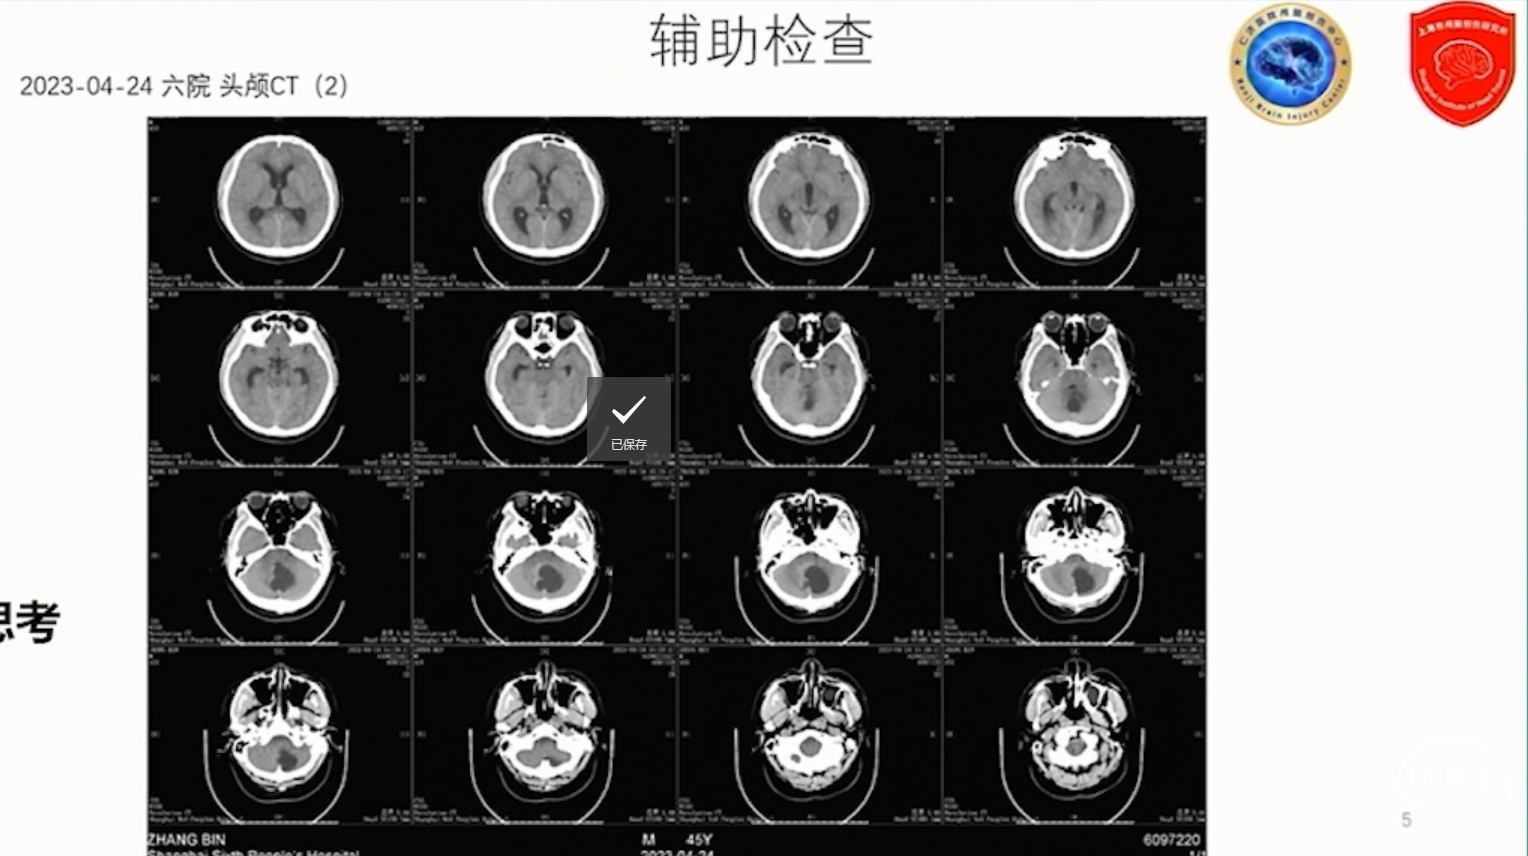

内镜下小脑血管母细胞瘤手术方式的思考

上海交通大学医学院附属仁济医院 杨溪教授